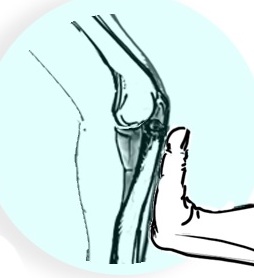

Patient supine with hand over head - examiner at head of bed - elbow fully extended and forearm supinated - elbow resembles knee in this position

Valgus stress with axial load & slowly flex elbow - at 30 - 45o the radial head subluxes posterolaterally - patient feels apprehension / pain - reduces as the elbow flexes more